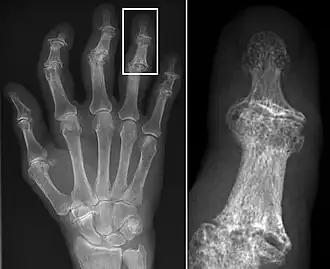

Osteoarthritis (OA) is a degenerative joint disease that affects the junctions of articulating elements, or synovial joints (e.g. knee, shoulder) and is characterized by the damage of cartilage. OA is the most commonly documented pathology found in archaeological human remains and has been used extensively as an activity marker that reflects stress-related activity patterns or occupation.[11] Factors such as age, sex, body size and others also affect its expression.[12]